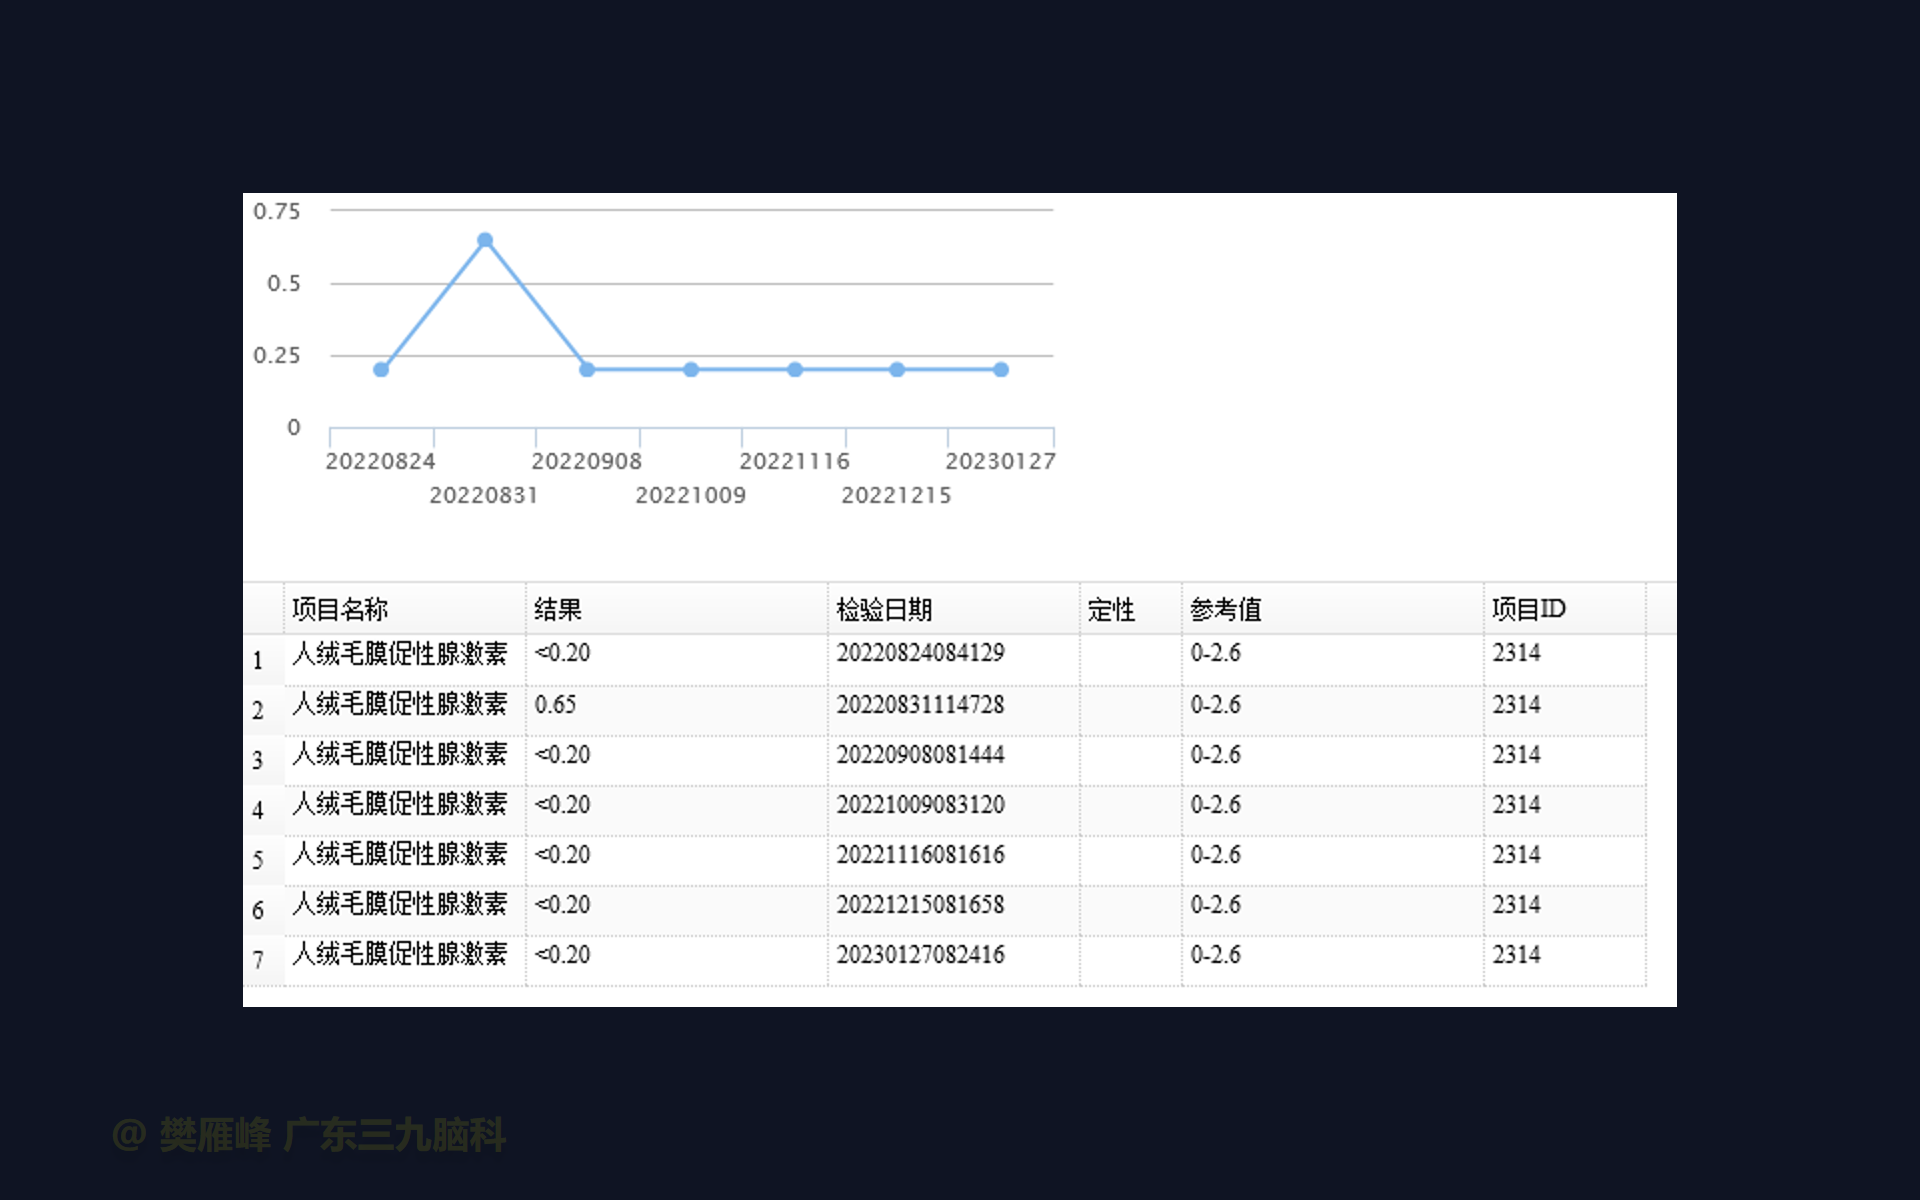

在这个二维手术视频中,展示了2例神经内镜下三脑室底造瘘+活检治疗三脑室后部肿瘤的方法。患者均为三脑室后部病变导致的梗阻性脑积水,病理结果1例为生殖细胞瘤,1例为淋巴瘤,在经过术后的放化疗病情均得到控制,生活质量满意。我们展示了安全的病变活检和第三脑室造瘘的技术要点,以最大限度减少术后继发脑积水和早期并发症。